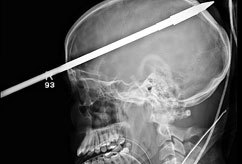

"친구 때문에…" 머리에 작살 관통 '끔찍' 입력 : 2012-06-22 10:39:06 수정 : 2012-06-22 10:39:06 구글 네이버 유튜브 미국 마이애미 대학 잭슨 메모리얼 병원이 제공한 사진으로 사고로 야세르 로페즈(16)의 머리를 관통한 작살이 보인다. 잭슨 메모리얼 병원의 라이더 외상 센터에 있는 로페즈는 19일(현지시간) 중태다. 병원 관계자들은 로페즈의 친구가 실수로 작살 총을 쐈다고 전했다. 로페즈는 지난 7일 작살이 이마에서부터 약 91㎝ 관통된 채 외상 센터로 이송됐다. Copyright ⓒ 세계일보. 무단 전재 및 재배포 금지 박지민